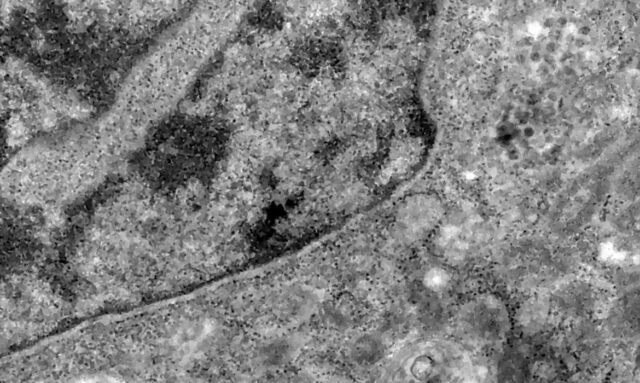

Pesquisadores brasileiros conseguiram, pela primeira vez, detectar a presença do coronavírus em retinas. O estudo pode contribuir para compreender melhor a dinâmica do vírus e as sequelas em pacientes infectados.

Os pesquisadores analisaram retinas de pacientes que morreram em decorrência da covid-19 e compararam com fotos dos olhos desses pacientes quando vivos para analisar as diferenças e formas de aferir a presença do vírus a partir da retina.

Foto – Fiocruz